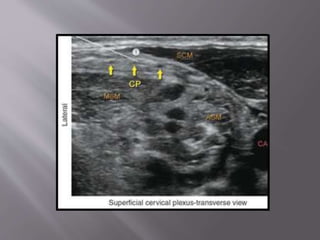

 Basically ultrasound guided superficial cervical

plexus block

 Ensures deeper components of the SCP are

anesthetized

 Position: Supine/Sitting

 Landmarks: Posterior border of the

sternocleidomastoid muscle at the level of the

external jugular vein

 Local: 5-15 mL